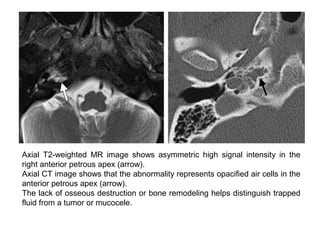

Axial T2-weighted MR image shows asymmetric high signal intensity in the

right anterior petrous apex (arrow).

Axial CT image shows that the abnormality represents opacified air cells in the

anterior petrous apex (arrow).

The lack of osseous destruction or bone remodeling helps distinguish trapped

fluid from a tumor or mucocele.